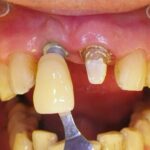

En este caso se trata de una paciente que recibió un bochazo de Hockey en la adolescencia y tuvo una prótesis fija durante más de 20 años.